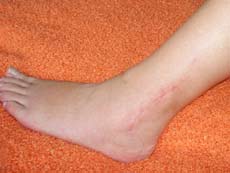

Zurück zur Lausitz 2008